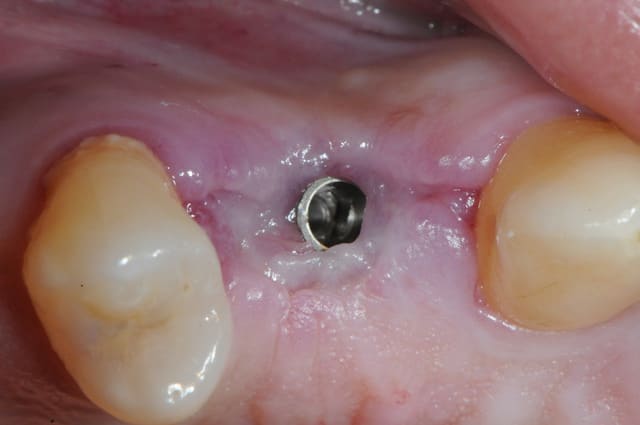

dis moi la tu le trouves comment mon compromis avec l'espace biologique

eii

d'après toi faites il y a combien de temps?

Superbe ratrapage suite à une operculisation d'une vis de couverture. Félicitations. Je te savais costaud béotien mais là tu m'impressionnes vraiment.

Je dirais fait il y a 11 ans 1/2? Alors.

- pas de vis de couverture , pas d'operculisation!!

Même pas de lambeau pédiculé palatin!